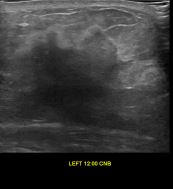

상기환자는 외부검사 이상소견으로 내원하신 60대후반 여성분으로 의심스러운 좌측혹 조직검사 시행해 유방암 진단되었습니다.